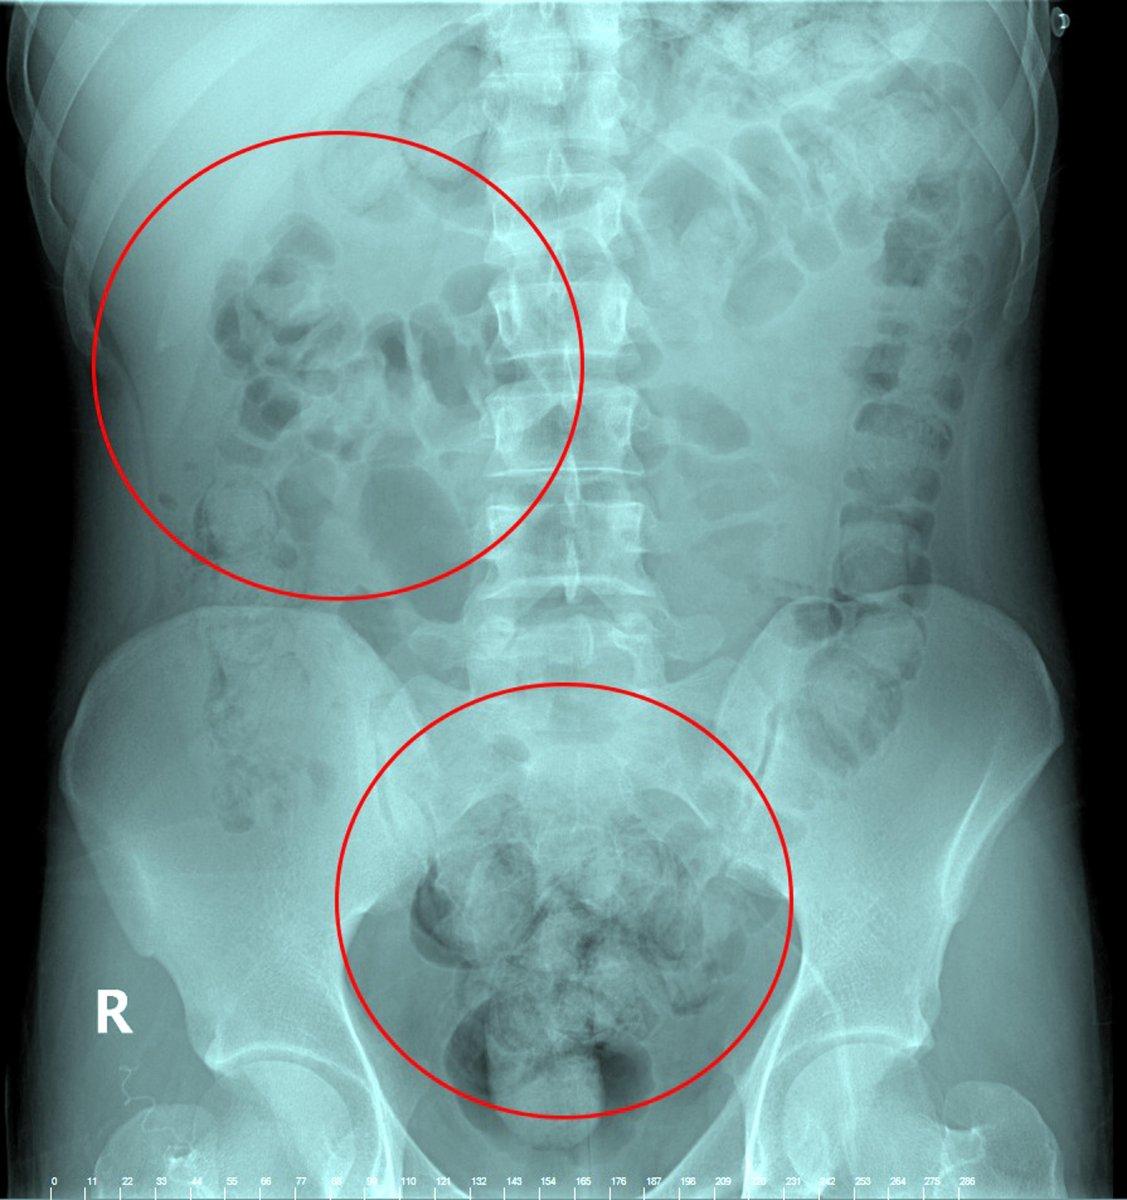

2'Sİ PATLAMIŞ 72 KAPSÜL ÇIKARILDI

Tedavi altına alınan Narziveh'in çekilen röntgen filminde midesinde cisim tespit edildi. Ameliyata alınan Zarziveh'in midesinden 2'si patlamış 72 adet kapsül halinde uyuşturucu madde çıkarıldı.

Doktorlar durumu polise bildirdi. Gelen polis ekiplerinin yaptığı incelemede 890 gram uyuşturucu maddenin metamfetamin olduğu belirlendi.